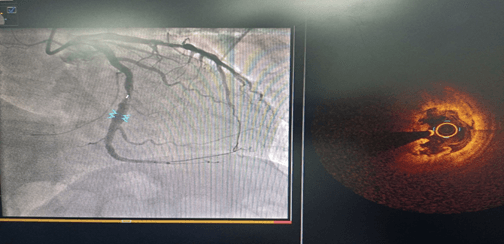

術(shù)前CAG示:LCX中段80%狹窄 ;OCT示纖維斑塊,最小管腔面積3.1mm2

術(shù)后OCT示:支架貼壁及膨脹良好,無夾層及血腫